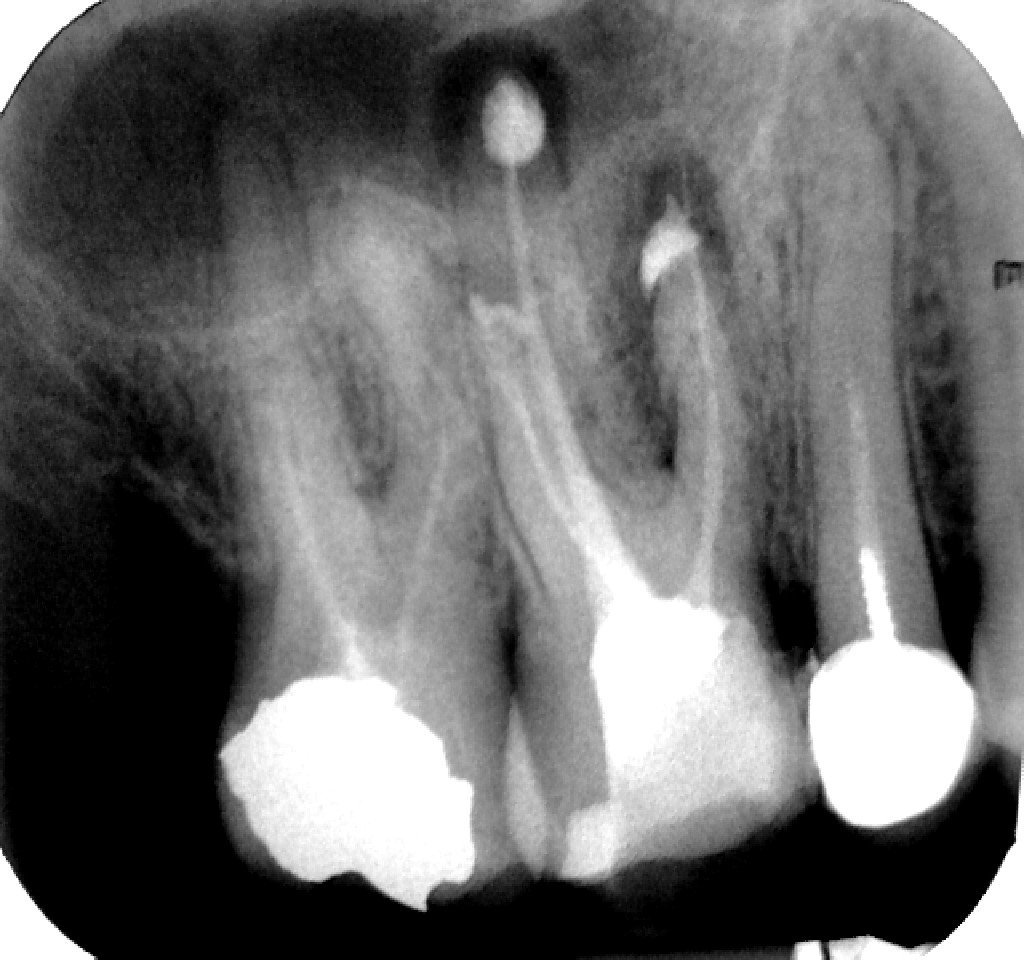

Добре ли са запълнени каналите на 6-ти горен зъб, след лекуване на гранулом ?